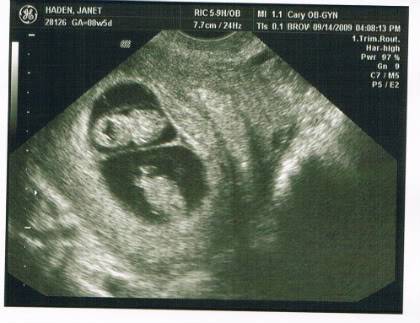

I wasn't expecting this today:

I was just getting comfortable with the idea of 1 - but 2 babies is crazy!

She's 9 weeks so still a ways to go...not sure if 2 car seats in the FJC is going to fly - might have to upgrade, ha!